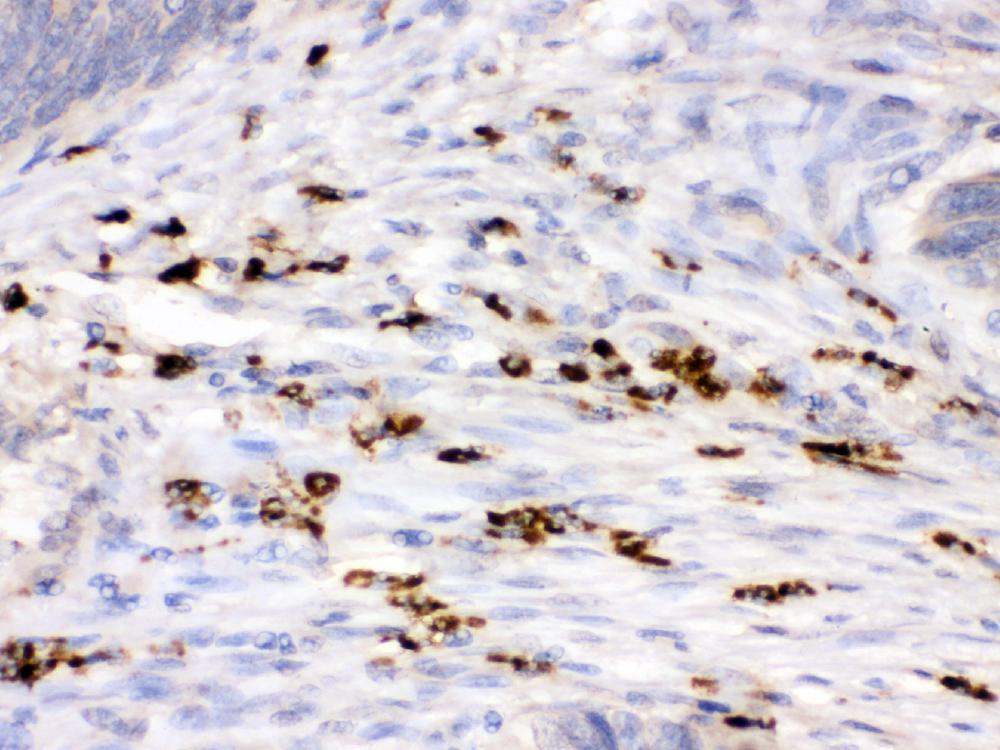

IHC analysis of Lysozyme/LYZ using anti-Lysozyme/LYZ antibody (PB9663) .

Lysozyme/LYZ was detected in a paraffin-embedded section of human intestinal cancer tissue. The tissue section was incubated with rabbit anti-Lysozyme/LYZ Antibody (PB9663) at a dilution of 1:200 and developed using HRP Conjugated Rabbit IgG Super Vision Assay Kit (Catalog # SV0002) with DAB (Catalog # AR1027) as the chromogen.